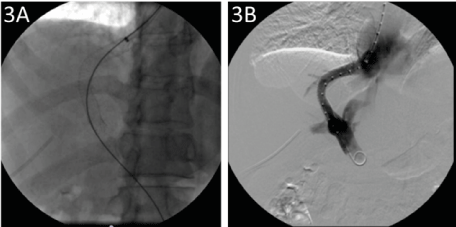

Total gastrectomy with curative intent is indicated based on the pathological findings, upper gastrointestinal endoscopy, and negative dissemination study. However, its performance implies a high risk of variceal bleeding, putting the patient’s life at risk. On the other hand, despite its effectiveness, endoscopic treatment of gastroesophageal varices is not an adequate strategy in this patient because it causes anatomical distortion, and complex surgical management in the tissues esophagojejunanastomosis will be performed. In this context, and to achieve curative treatment, we decided to decrease portal pressure prior to surgery by installing TIPS (Figure 3). Specifically, we proceeded to install TIPS portocava, which passed without incident.

Figure 3. Radiological evidence of TIPS installation. (A) Fluoroscopy in which the release of a self-expanding metallic stent 10 mm x 8 cm is visualized with its ends in the right suprahepatic vein and the right portal vein (white arrow). The access with a 5 French sheath in the right portal vein branch is also identified. (B) Fluoroscopy with subtraction showing permeability of the TIPS, well-positioned. A metallic stent is observed, with an in situ measurement system and access with a 5 French sheath in the right portal vein branch